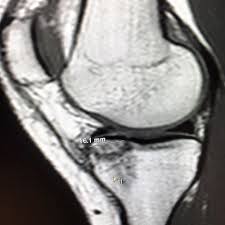

The details surrounding the crash remain somewhat murky, with witnesses describing a loss of control on a particularly challenging section of the Austrian course. While video replays are currently being reviewed by officials to determine the precise cause, the impact was clearly significant enough to necessitate immediate medical intervention. Initial assessments revealed a tibial plateau fracture - a break in the upper part of the shinbone - alongside substantial bruising and suspected ligament damage. Medical professionals are diligently evaluating the extent of the ligament damage, a factor that will heavily influence the long-term prognosis.